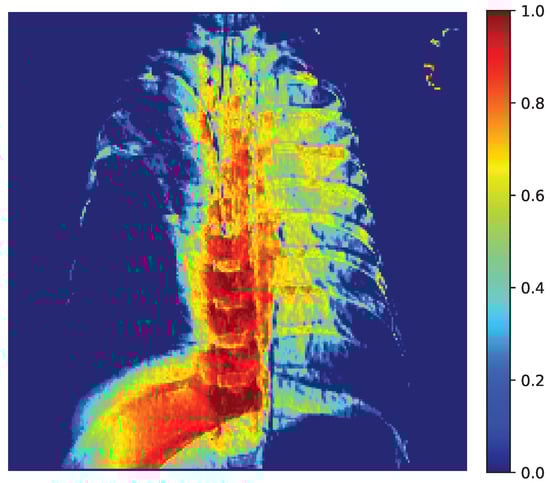

3.8. Explainability Analysis